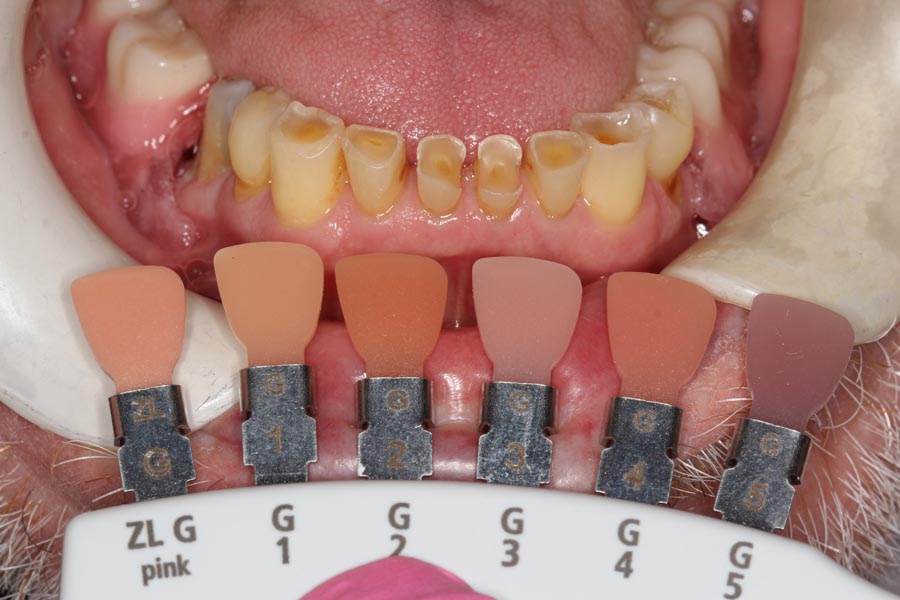

Matching of the gum tissue color is one more step we take in the “customization” process. Most offices have only two choices for the gum color.